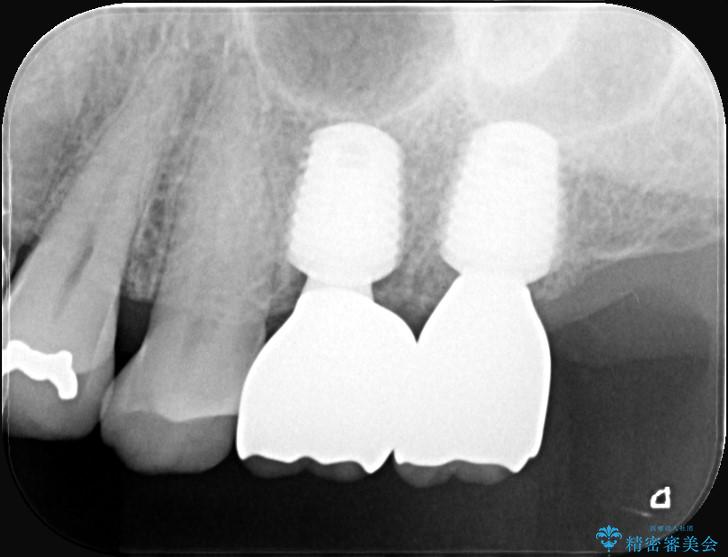

7番については抜歯と同時にインプラントを埋入する「抜歯即時埋入法」を選択。通院回数と治療期間を大幅にカットすることで患者様の負担を減らします。

あわせて6番目にもインプラントを行い、奥歯でしっかり力強く噛める状態を整える計画です。